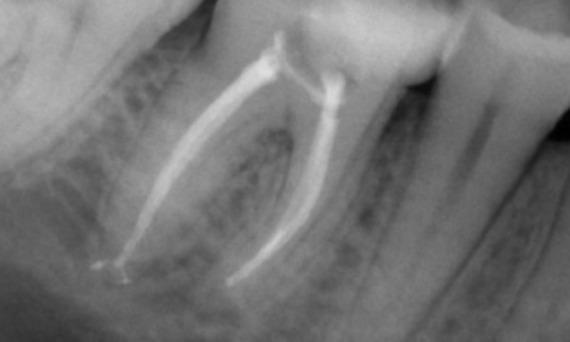

Antes: Radiolucencia periapical asociada principalmente con la raíz distal y pérdida de la lámina dura en la raíz mesial.

Después: En este caso, se eligió TruNatomy para permitir un enfoque apalancado en las caries y un enfoque en la conservación de la dentina pericervical, especialmente en el aspecto mesial donde el diente tuvo una restauración más mínima.

Dr. Jonathan Cowie (especialista en endodoncia)

Bath, Reino Unido